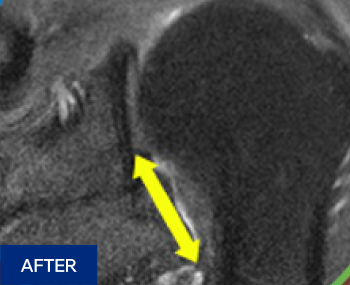

수술 상처 없이 간단한 시술로 관절막을 열어줍니다.

마취 후 전문 의료진이

어깨를 6방향으로

움직여 유착 해소

5~20분 소요

무절개, 빠른 회복

시술 중, 시술 후

빠른 통증 경감과

운동 범위 회복